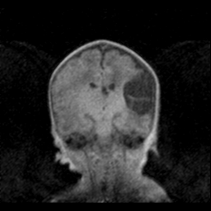

A special pod which is compatible with the RF coils is provided to hold the baby safely within the magnet. MR compatible vital signs monitoring is included and both visual monitoring and emergency access are excellent as seen in the image above. The system is so quiet there is no need for hearing protection and the SAR is also so low as to be insignificant even for very low weight premature babies. Over 600 studies have been safely carried out without use of sedatives or general anaesthetics at the NICU in Sheffield, UK. Research studies have shown that the system can provide up to 50% more diagnostic information than 'gold-standard' ultrasound*. A complete solution for neonatal MRI.